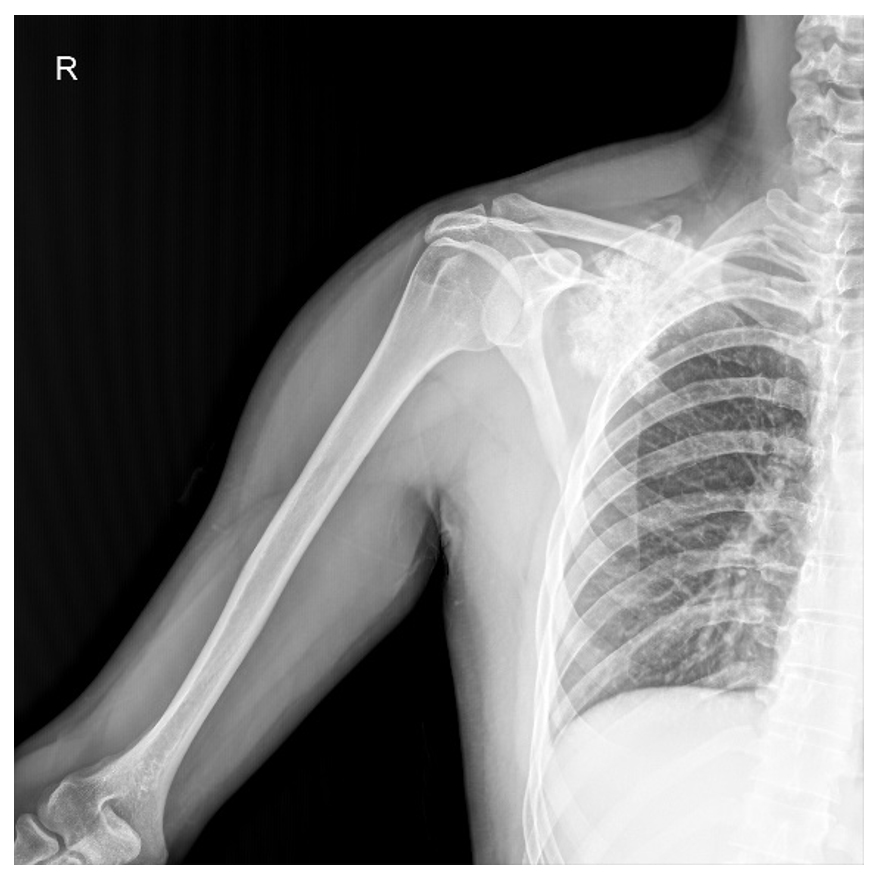

Ameliyat Öncesi: Röntgende skapula üzerinde düzensiz sınırlı heterojen kitle görünmekte.

Ameliyat Sonrası: Röntgende ve tomografide tümör çıkarıldıktan sonra kalan skapula görülmekte.